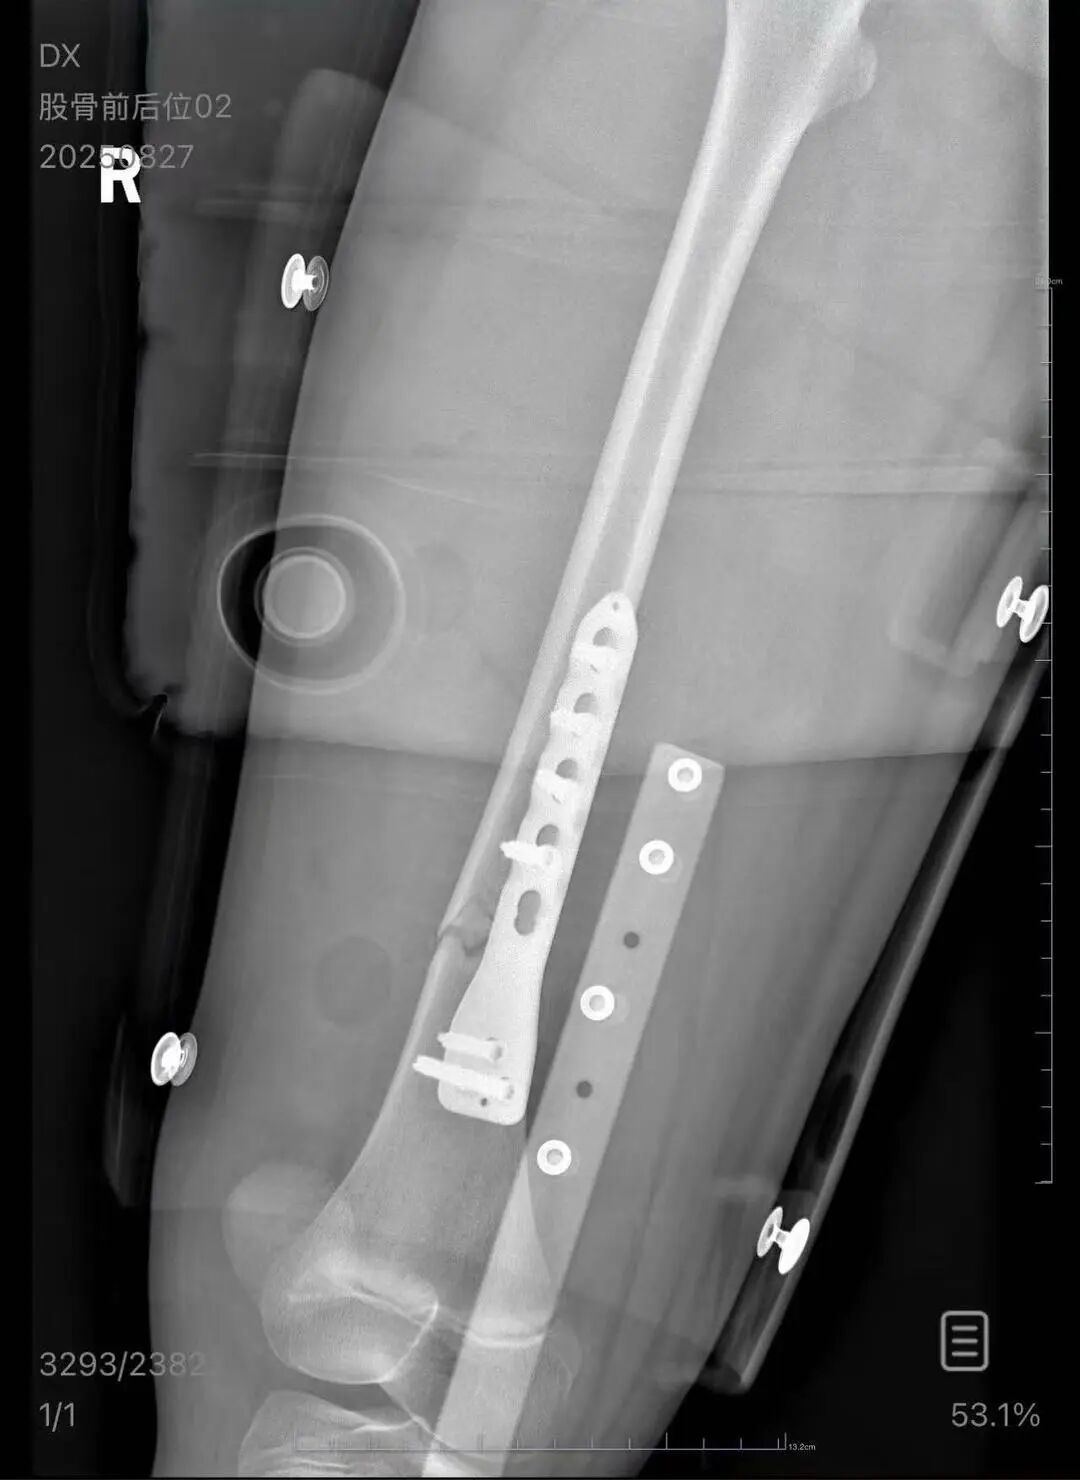

▲朱女士女儿手术后拍的X光片 受访者供图

朱女士向记者出示的医院病历显示,8月24日凌晨,朱女士的女儿到医院就诊。医院诊断朱女士的女儿右股骨骨折,需要住院进一步治疗。

朱女士告诉扬子晚报/紫牛新闻记者,医疗费加上护工费已经花费了5万多元,“而且在出院以后,医生说因为植入了钢板,后续孩子可能会有后遗症,最有可能出现的是长短腿,让我们去做康复治疗,这就面临着另一笔费用。”